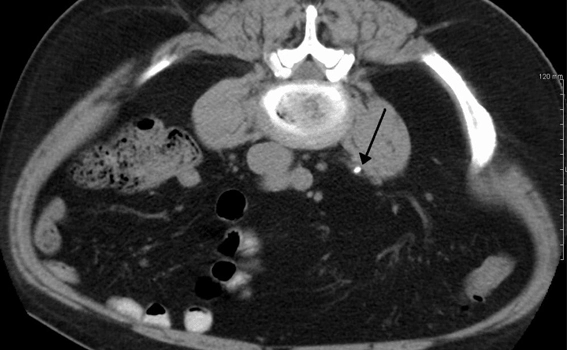

• CT Scan:

Provides a clear and detailed image of the stone to guide treatment.